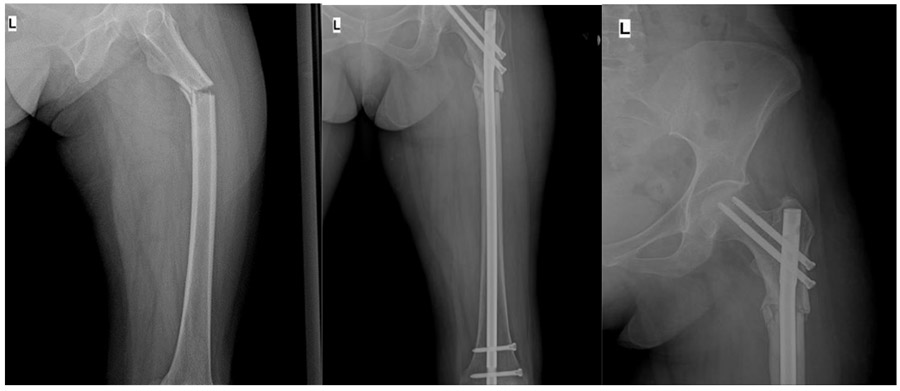

CASE 33: Risk of fracture and fracture development due to breast cancer metastasis to the upper end of the left thigh (femur).

Before and after surgery: The X-ray shows fracture development due to metastasis, and the fracture was closed and fixed with a titanium nail.